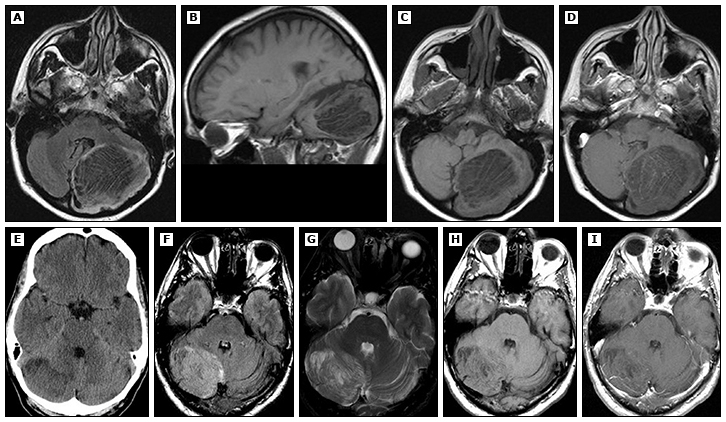

影像学特点:虎纹征

1、虎纹征 :LDD的占位效应明显,可累及小脑蚓部、桥臂、第四脑室等结构,造成不同程度的梗阻性脑积水,部分可导致小脑扁桃体下疝。“虎纹征”为LDD 的典型MRI表现,T1WI 呈条纹状相间的等、低信号或层状排列结构,T2WI 呈条纹状相间的等、高信号,表现为在高信号区域里可见低信号的条纹状结构,即为“虎纹征”;这是由于小脑叶片异常神经元细胞的增生和过度髓鞘化,以及中央白质萎缩形成的疏松结构间的脑脊液所致。增强扫描见线样、条状强化或无强化病变,病变的强化可能与蛛网膜下腔小血管的异常有关。

2、肿瘤无强化:也是LDD的特征性MRI表现,由于病变区血脑屏障无明显破坏,无细胞外水肿,因此增强后肿瘤无明显强化。